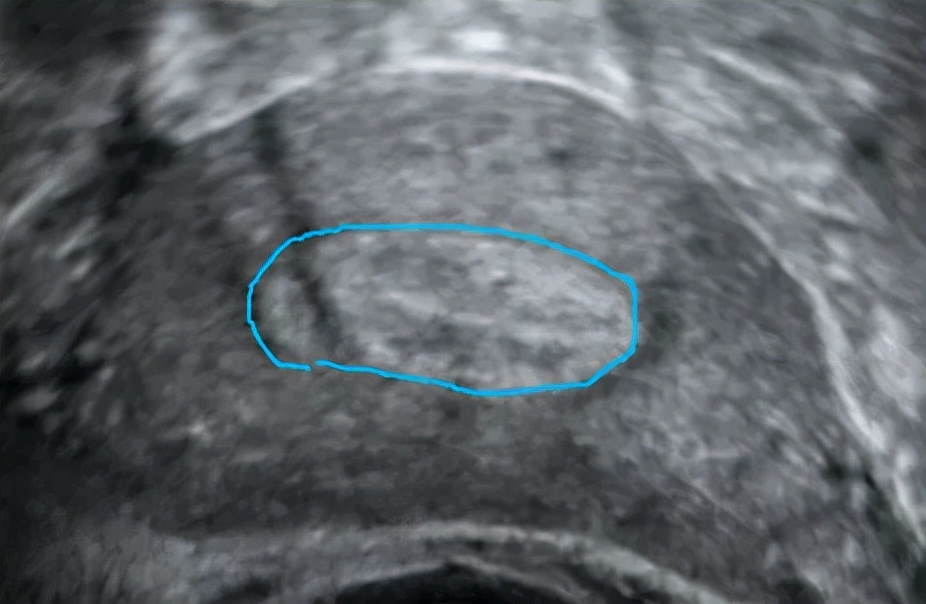

画蓝线的地方是正常内膜的范围